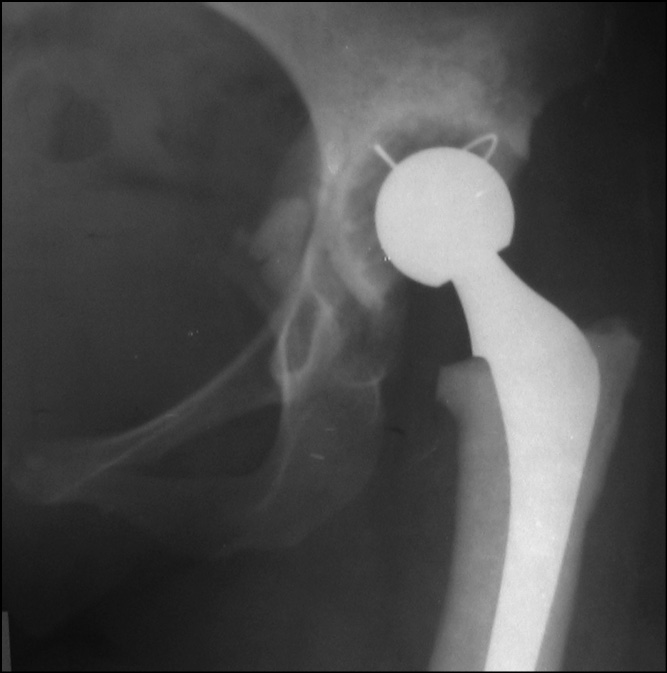

Пациентка в возрасте 45 лет поступила в ФГБУ «Национальный медицинский исследовательский центр травматологии и ортопедии им. Н.Н. Приорова» (ЦИТО) в 2019 г. с жалобами на боли, ограничение движений в области правого тазобедренного сустава и нарушение походки. Из анамнеза известно, что с 3-летнего возраста по поводу врожденного вывиха тазобедренных суставов наблюдалась у ортопеда по месту жительства. В возрасте 5 лет выполнены реконструктивные операции тазобедренных суставов (выписки не представлены). До 16-летнего возраста беспокоили периодические боли в тазобедренных суставах, больше справа. В 1991 г. в ЦИТО выполнено первичное тотальное эндопротезирование правого тазобедренного сустава эндопротезом фирмы ESKA Implants. В послеоперационном периоде без особенностей, рана зажила первичным натяжением. Функцией сустава пациентка была довольна до 1997 г., когда появились и стали прогрессировать боли в области оперированного сустава (рис. 1).

Рис. 1. Рентгенограмма правого тазобедренного сустава на момент поступления в клинику в 1998 г.

В 1998 г. по поводу нестабильности вертлужного компонента тотального эндопротеза правого тазобедренного сустава выполнено ревизионное эндопротезирование, установка чашки цементной фиксации (рис. 2).

Рис. 2. Рентгенограмма правого тазобедренного сустава после ревизионного эндопротезирования, замена вертлужного компонента в 1998 г.